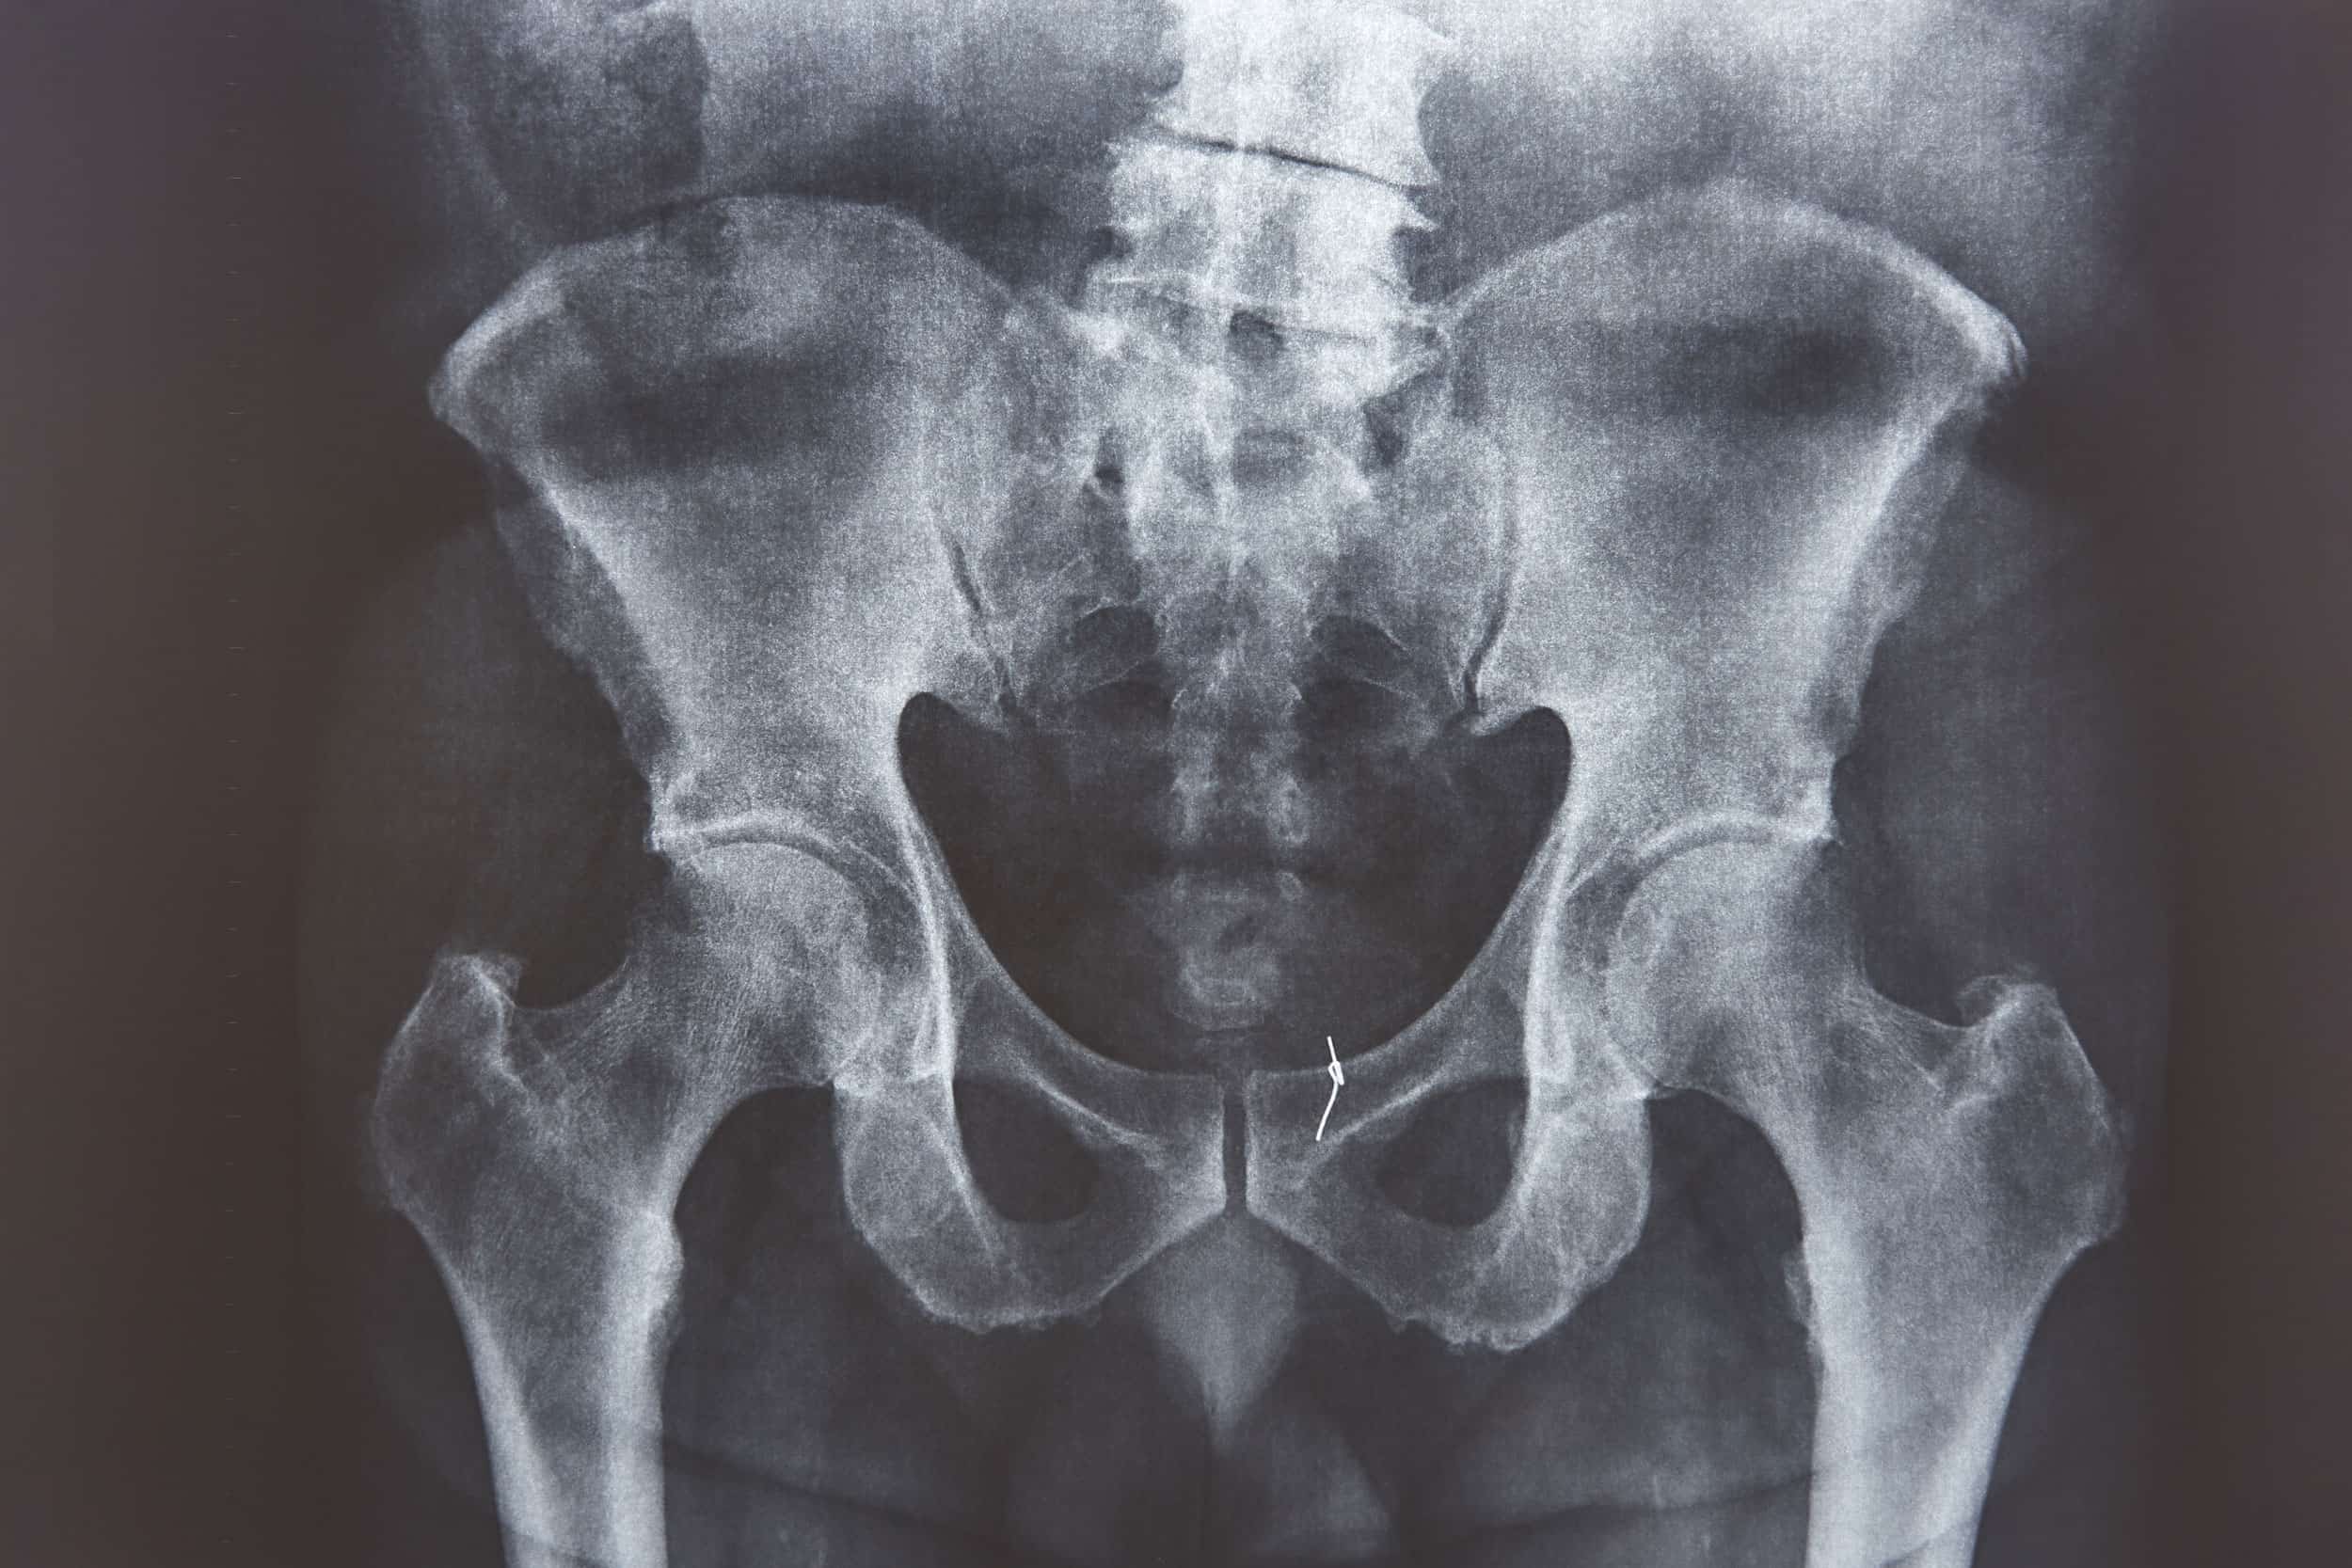

Articulation centrale entre le bassin et la jambe, la hanche joue un rôle essentiel dans la posture, la marche et la course. Quand elle devient douloureuse, c’est tout l’équilibre corporel qui est perturbé.

Raideur le matin, gêne à la marche ou en position assise, douleurs après le sport… Les douleurs de hanche touchent aussi bien les jeunes sportifs que les personnes âgées.